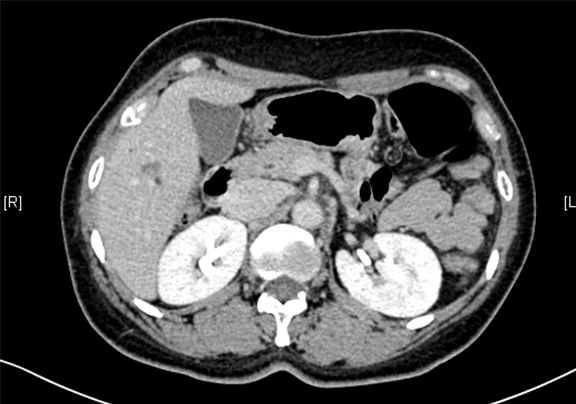

术前CT检查:动脉期

静脉期

平衡期